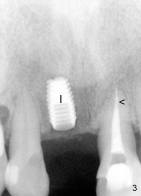

This article reports design of a simple semilunar incision for implant uncover to help form a natural-looking gingiva around anterior crown. A fifty-year-old lady has severe periodontal disease, complicated with endodontic lesion of the teeth #8 and 9 (Fig.1,2). #8 is extracted and Bicon 4.5x8 mm implant (Fig.3: I, Boston, Massachutte) is placed with bone expansion (Tatum Surgical, Clearwater, Fl) 1 year later . After RCT retreatment for #9 (compare Fig.2,3: black arrowheads), periapical radiolucency (Fig.2: red arrowhead) resolves (Fig.3).